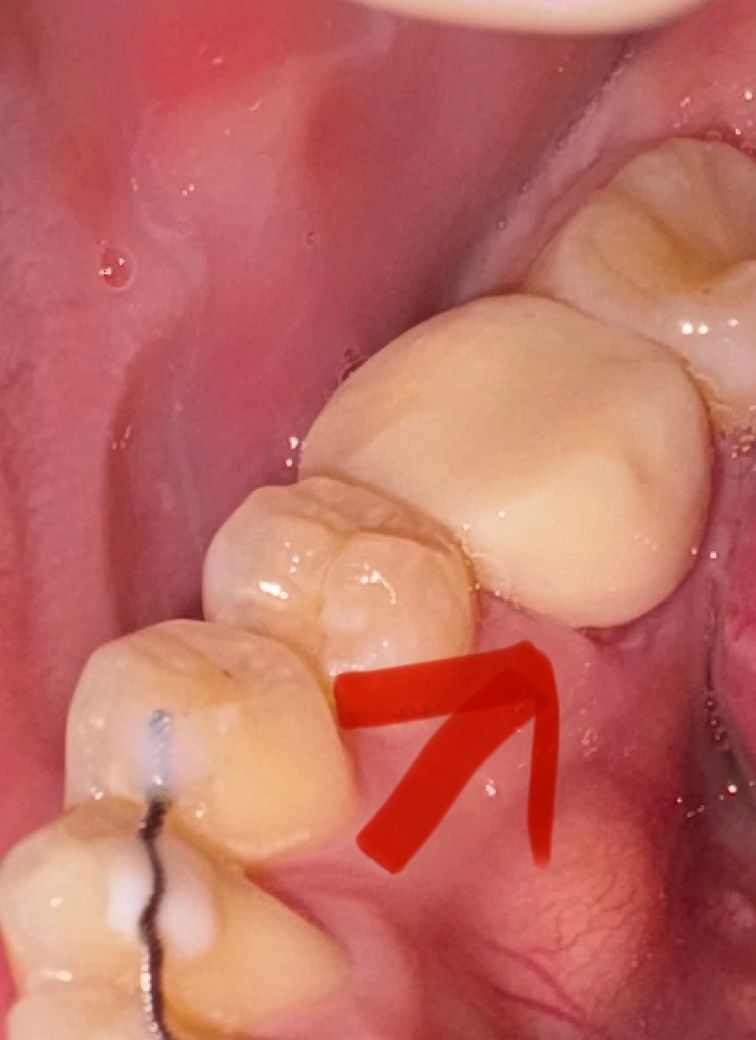

신경치료 중이구 임시치아 씌어 놨는데

혹시 이 임시치아 들뜬건가요? 치과 갈 시간이 없어서 급하게 여쭤봅니다 ㅠ 안으로 세균 들어갈까봐요.............

들뜬건 아니고 잇몸의 붓기가 빠지면서 그러는거 같습니다. 실제 보철물은 딱 맞게 나오니 너무 걱정하지마세요.

임시 치아는 경계 부위가 뜨거나 할 수 있습니다. 크게 문제가 되진 않으며 나중에 보철물을 제작할 땐 해당 부위가 뜨지 않도록 제작하게 됩니다.

임시치아 자체가 들떴다기보다는 약간 짧게 치아를 다 덮지 못하게 만들어진 것 같습니다

금방 최종 보철물을 만든다면 크게 상관은 없습니다